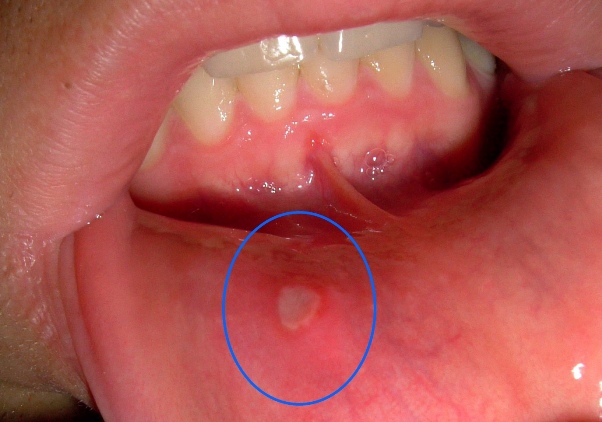

Afte su male, bolne ulceracije koje se najčešće javljaju u usnoj šupljini, posebno na unutrašnjim dijelovima usana, jeziku i sluznici obraza. Ove ranice, iako sitne, mogu uzrokovati značajne nelagode, otežavajući nam svakodnevne aktivnosti poput jela, razgovora i pijenja. Većina ljudi doživljava afte kao prolaznu prepreku, ali za mnoge, one mogu postati ozbiljan izvor stresa i nelagode. U ovom članku istražujemo uzroke nastanka afti, prirodne tretmane koji vam mogu pomoći, kao i savjete za prevenciju kako biste izbjegli njihovo ponavljanje.

Postoji nekoliko prirodnih lijekova koji mogu pomoći u ublažavanju simptoma afti. Aloe vera je jedan od najpoznatijih prirodnih tretmana zbog svojih protuupalnih svojstava. Nanesite nekoliko kapi soka aloe vera direktno na aftu nekoliko puta dnevno. Nakon primjene, preporučuje se da izbjegavate unos hrane i pića kako bi aktivni sastojci imali vremena da djeluju. Pored aloe vera, soda bikarbona se također pokazala kao efikasna metoda. Pomiješajte sodu bikarbonu s malo vode kako biste dobili pastu, koju potom nanosite na aftu. Ova metoda smanjuje bol i upalu, a ispiranje usta toplom vodom nakon nekoliko minuta može dodatno pomoći. Korijander je još jedan prirodni lijek koji sadrži antimikrobne komponente. Prokuhajte nekoliko listova korijandera u vodi i koristite ovaj čaj za ispiranje usta. Također, ponekad se preporučuje i ispiranje usta slanom vodom, što može pomoći u smanjenju upale i ubrzati proces ozdravljenja.